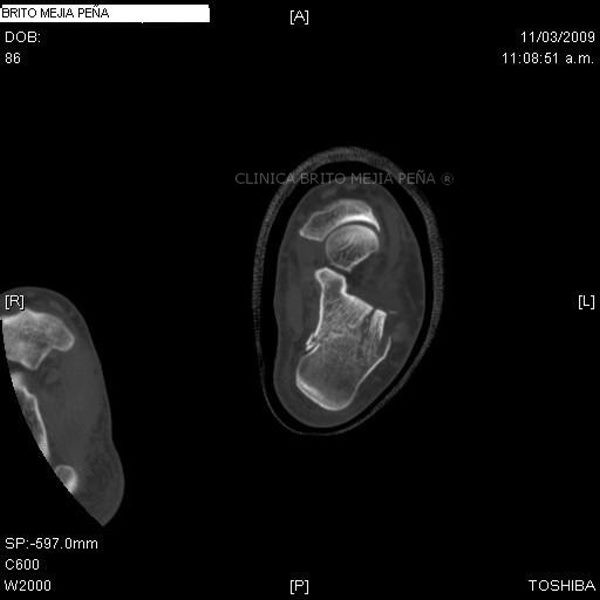

Pié normal anterior

Pié normal posterior